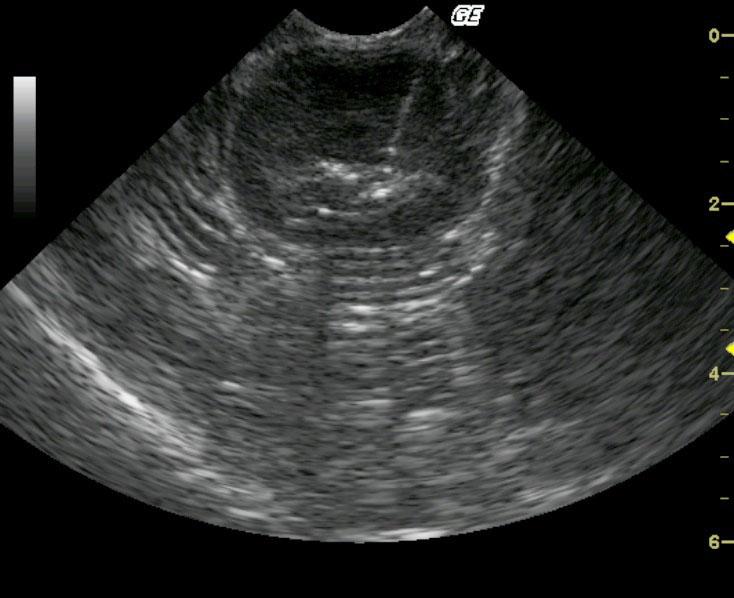

This MN 10-year-old DSH was presented for partial anorexia and weight loss and the physical examination revealed palpably thickened intestines. A CBC and blood chemistry profile revealed a mild leukocytosis with slightly elevated ALT and slightly elevated lipase.